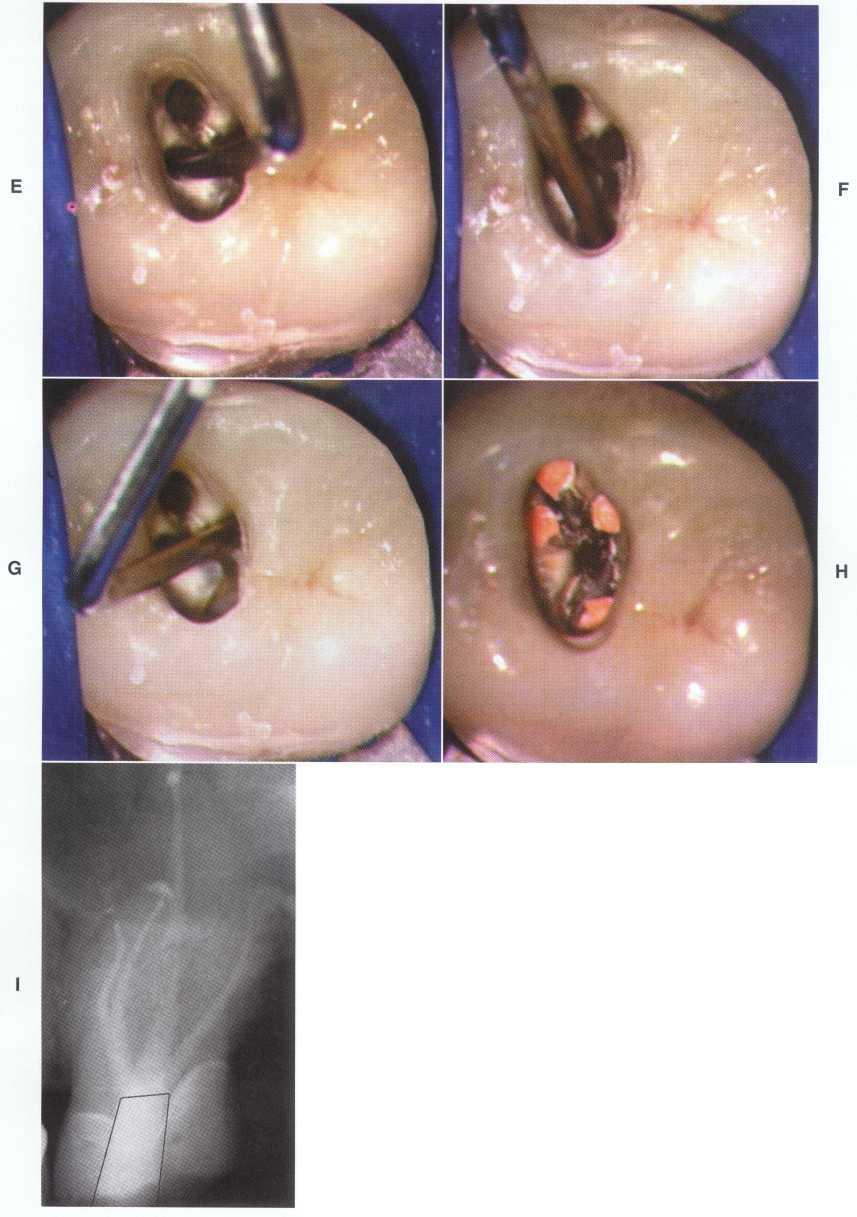

Unroo fing the Chamber

Unroofing the chamber and removing the coronal pulp facilitates the clinician's ability to visualize the chamber floor and aids in locating the canals. Complete removal of tissue and debris prevents discoloration and subsequent infection.

Unroofing the chamber and removing the coronal pulp (in vital cases) allow the clinician to see the pulpal floor. In cases of patent canals, most or all of the canal orifices may be easily located before the chamber is completely unroofed, but the clinician may nevertheless miss canals. In cases of calcification, performing these procedures increases the clinician's ability to visualize the pulpal floor and read the road map to the canal orifices detailed in the subtle color changes and patterns of calcification left by the receding pulp. This is extremely difficult or impossible to do through a "mouse hole" en-dodontic access.

Removal of the Coronal Pulp

Removal of the coronal pulp so that the canals may be located is necessary in cases with vital pulp. One advantage of removing the coronal pulp is that the radicular fragments may hemorrhage slightly, aiding in location of the canal orifices. This is especially useful in maxillary molar cases for locating the second mesiobuccal (MB2) canal.